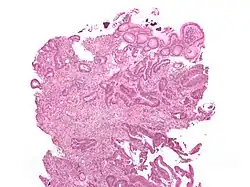

Microfoto de colônia carcinóide, manchado em hematoxilina e eosina.

Microfoto de uma metástase colorretal em um nódulo linfático. As células cancerosas estão no topo esquerdo e no centro da imagem.

As chances do tratamento ser eficiente dependem do estádio do cancro. No geral, 90% dos pacientes que são diagnosticados com cancro em estádios iniciais sobrevivem cinco anos, caindo para 64% se o tumor invadiu nódulos linfáticos e/ou órgãos próximos.[14] Quando o cancro é diagnosticado em estádio avançado, com metástases distantes, a taxa de sobrevivência de cinco anos é de 20%.

Microfoto de um adenoma viloso colorretal. Estas lesões são consideradas pré-cancerígenas.

O objetivo do monitoramento pós-tratamento (ou follow-up) é diagnosticar o mais rápido possível quaisquer metástases ou tumores que desenvolveram-se posteriormente, mas não se originaram do tumor original. A ASCO e o National Comprehensive Cancer Network dão as seguintes recomendações para o follow-up do cancro colorretal.[73][74] Uma história médica em conjunto com uma examinação física são recomendadas a cada três a seis meses, por dois anos, e após, a cada seis meses, por cinco anos. Exame de nível de antígeno carcinoembriônico no sangue segue o mesmo padrão de tempo, mas é somente aconselhável em pacientes com T2 ou lesões mais severas, e que são candidatos a cirurgia curativa. Tomografia computadorizada do peito, abdômen e do pélvis pode ser considerado anualmente nos primeiros três anos para pacientes com alta chance de recorrência (por exemplo, pacientes com tumores pouco diferenciáveis ou invasão venosa e/ou linfática), pós-cirurgia. Uma colonoscopia pode ser realizada após um ano, exceto se este procedimento não pôde ser realizado como método de estagiamento; neste caso, uma colonoscopia deve ser realizada três a seis meses após a cirurgia. Se um pólipo viloso, pólipo com mais de um centímetro, ou uma displasia de alto grau são encontrados, a colonoscopia pode ser repetida após três anos, e então, a cada cinco anos. Para qualquer outra abnormalidade, a colonoscopia pode ser repetida após um ano.